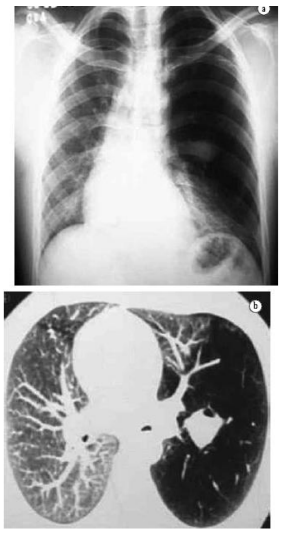

Analise as imagens para responder à questão

Enunciado 4906548-1

Em: https://jbp.org.br/details/147/pt-BR/chest-x-ray-and-computed-tomography-in-the-evaluation-of-pulmonary-emphysema;

A análise do corte axial evidencia uma estrutura tubular preenchida por muco, sem comunicação proximal com a via aérea central. Quanto à relação com o feixe broncovascular, assinale a opção correta:

Enunciado 4906546-1

Considerando o aspecto do parênquima adjacente à mucocele, indique a alteração vascular esperada na imagem: